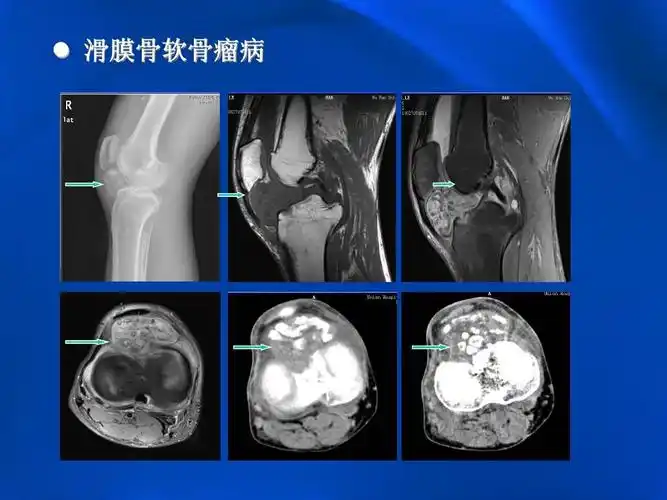

一例罕见的膝关节滑膜骨软骨瘤病

【过目不忘】滑膜骨软骨瘤病

滑膜骨软骨瘤病